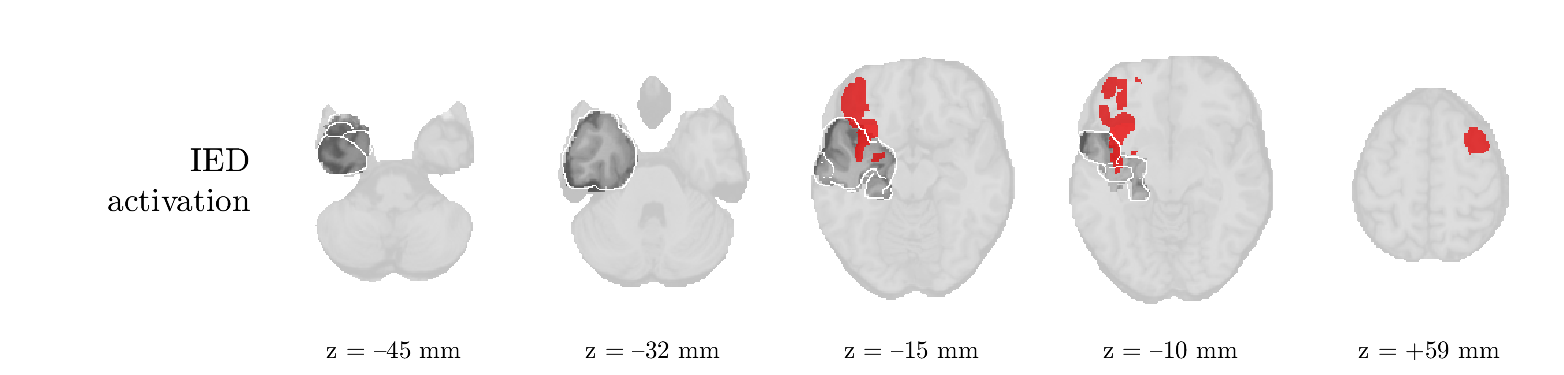

Patient 1

We analyze the solution with sources. Figure 1 shows the EEG signatures and HRF waveforms. One of the sources is highly correlated to the MWF reference (in grey), which was already known from Table B.3. This IED-related source had a typical low-frequency spectrum, which is expected for the typical spike-and-wave interictal discharges. The topography is relatively diffuse, although the highest amplitudes are mostly in the left hemisphere. This is in accordance with the lateralization of ictal onset zone (left temporal lobe, cfr. Table 1). There are some noteworthy observations to be made about some of the other components. The fourth has an unusually sharp spectrum, is mainly localized on two nonadjacent center electrodes, and is sustained for a single period of many seconds Hence, this component likely captured an artifact (of yet unknown origin), although we spotted no large-amplitude changes in the EEG itself. Similarly, the third source is only present at one frontal electrode, and exists in a frequency range above 20 Hz. It might represent a muscle artifact, e.g., due to frowning or twitching of some muscles in the forehead. The HRFs of all ROIs are shown in Figure 1(b). Two of the basis functions seem to have converged to a very similar waveform, which is an unfortunate possibility if two initial HRFs are too close to the same local optimum in their respective parameters. This reduces the expressive power of the basis set, which is clearly visible, since many ROIs have a nearly identical HRF. One of the twenty ROIs with the highest-entropy HRF overlapped the IOZ, although clearly this HRF (bold line) is not among the most dissimilar waveforms for this patient. This is also visible in Figure 2: both the HRF entropy and extremity maps show a small overlap with the delineated IOZ. Despite the good correspondence in the EEG domain, no significant (de)activation of the IED-component is found inside the IOZ.

Patient 2

We analyze the solution with sources, and show the results in Figure 3 and 4. As for patient 1, we found a source which is strongly correlated to the MWF envelope, and which had a mostly low-frequency behavior characteristic for spikes. The topography is mostly uninformative, and does not clearly correspond to the patient’s clinical data. The third source is mostly present at both sides of the head, is very sparsely active in time, and has a high-frequency content: this is most likely an artifact due to the neck muscles. Again, there is one of the highest-entropy HRFs which belongs to a ROI in the IOZ. Now, the waveform is clearly resolved from the other HRFs, through the strong initial dip (before 0 seconds). Such a dip is sometimes observed in HRFs, but its underlying physiological mechanism is not yet fully understood. It is possible that this dip reflects altered vascular autoregulation near the IOZ (cfr. the explanation in the Section 1 of the main text), or a rapid depletion in oxygen due to IED generation (before the IED becomes visible on the EEG). Figure 4 furthermore shows that the IED-related component is significantly active in parts of the IOZ, and deactive in others. As mentioned earlier, this deactivation may or may not be due to errors in sign correction. Interestingly, the ROI with the high alteration in neurovascular coupling is distinct from both the activated and deactivated ROIs.

Patient 4

We analyzed the solution with sources, and show the results in Figure 5 and 6. There is one source which is mostly correlated to the reference (but not extremely, see also Table B.3). This source had a right-temporal focus, conform the diagnosis in Table 1. The second source illustrates the phenomenon of an erroneous sign exchange between the spatial and spectral profiles. Also one of the HRFs has a negative polarity, which is a failure of the sign correction procedure (in this case, because there is exceptionally no positive overshoot). However, the HRF variability metrics are still interpretable, and indeed two ROIs among the ones with the highest-entropy HRFs overlap with the IOZ. The IED component is significantly active in a tiny portion of the IOZ (cfr. Figure 6). The second source is significantly active in symmetrical parts of the parietal lobe. Given its ongoing fluctuation over time, we hypothesize that this source captures a resting state network (RSN).